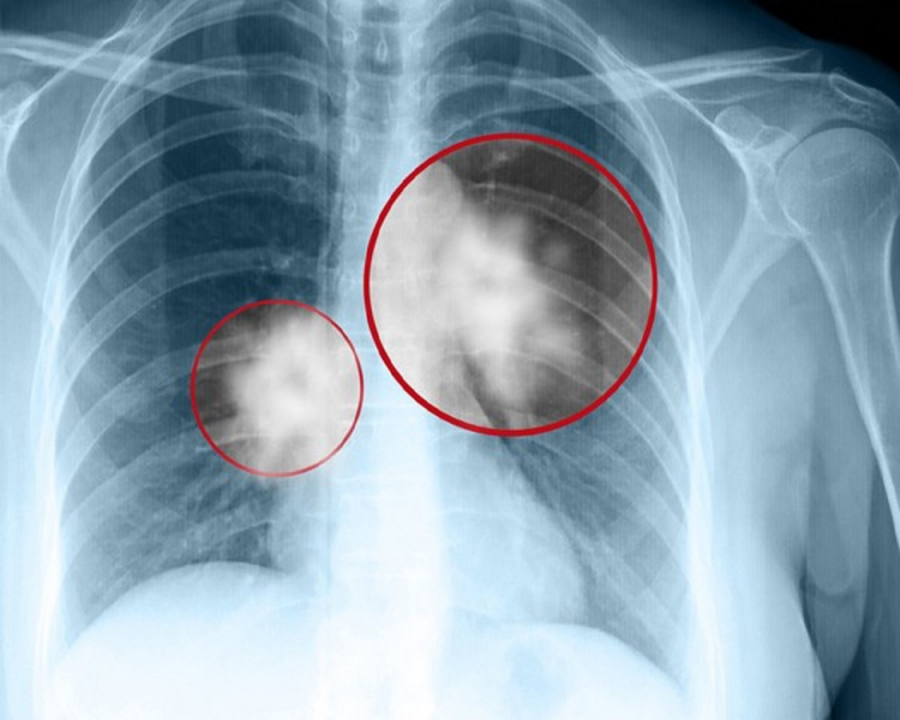

Ung thư phổi là một trong những căn bệnh cướp đi sinh mạng nhanh nhất. Thế nên khi bị chẩn đoán ung thư phổi thì kể như bị tuyên án tử hình. Thế nhưng, nếu biết được vị thuốc quý này bạn sẽ chẳng cần phải lo lắng.

Đây là hai triệu chứng thường gặp nhất ở các loại ung thư phổi. Nguyên nhân do khối u cản trở không khí khiến phổi gặp khó khăn khi hoạt động, máu không được cung cấp đủ oxy, gây ra tức ngực, khó thở.

Triệu chứng tức ngực trong giai đoạn đầu của ung thư phổi thường diễn ra không theo quy luật nào. Trong trường hợp cơ thể bạn thường xuyên xuất hiện cảm giác đau ngực dữ dội, điều này đồng nghĩa với ung thư đã phát triển tới giai đoạn cuối.